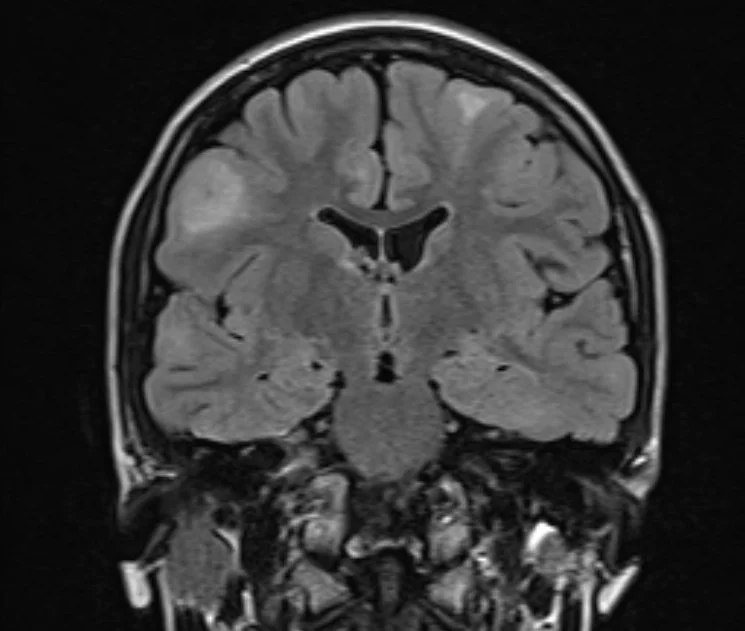

Cortical Tubers

• Benign hamartomas

• Triangular shaped lesion

• 80% are in frontal lobe

• T1: low signal,

• T2/FLAIR: high signal

• Can be iso-intense in neonatal period

• Enhancement is rare